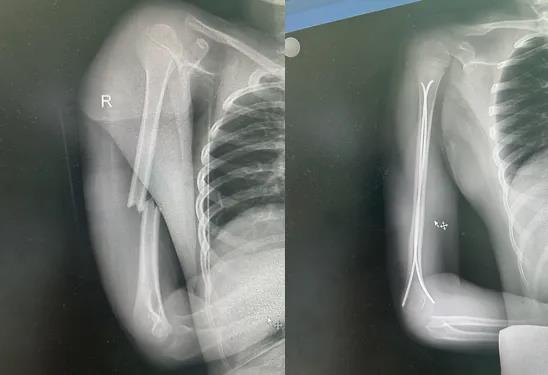

这是一种专门为儿童设计的骨折微创手术。医生仅在骨折肢体远端做两个不到2厘米的小切口,将两根具有良好弹性的钛合金髓内钉置入骨髓腔,像支架一样从内部将骨折端固定(见示意图)。它巧妙利用了“三点支撑”的力学原理,既能稳定骨折,又允许微动,特别适合儿童骨骼的生理特点。